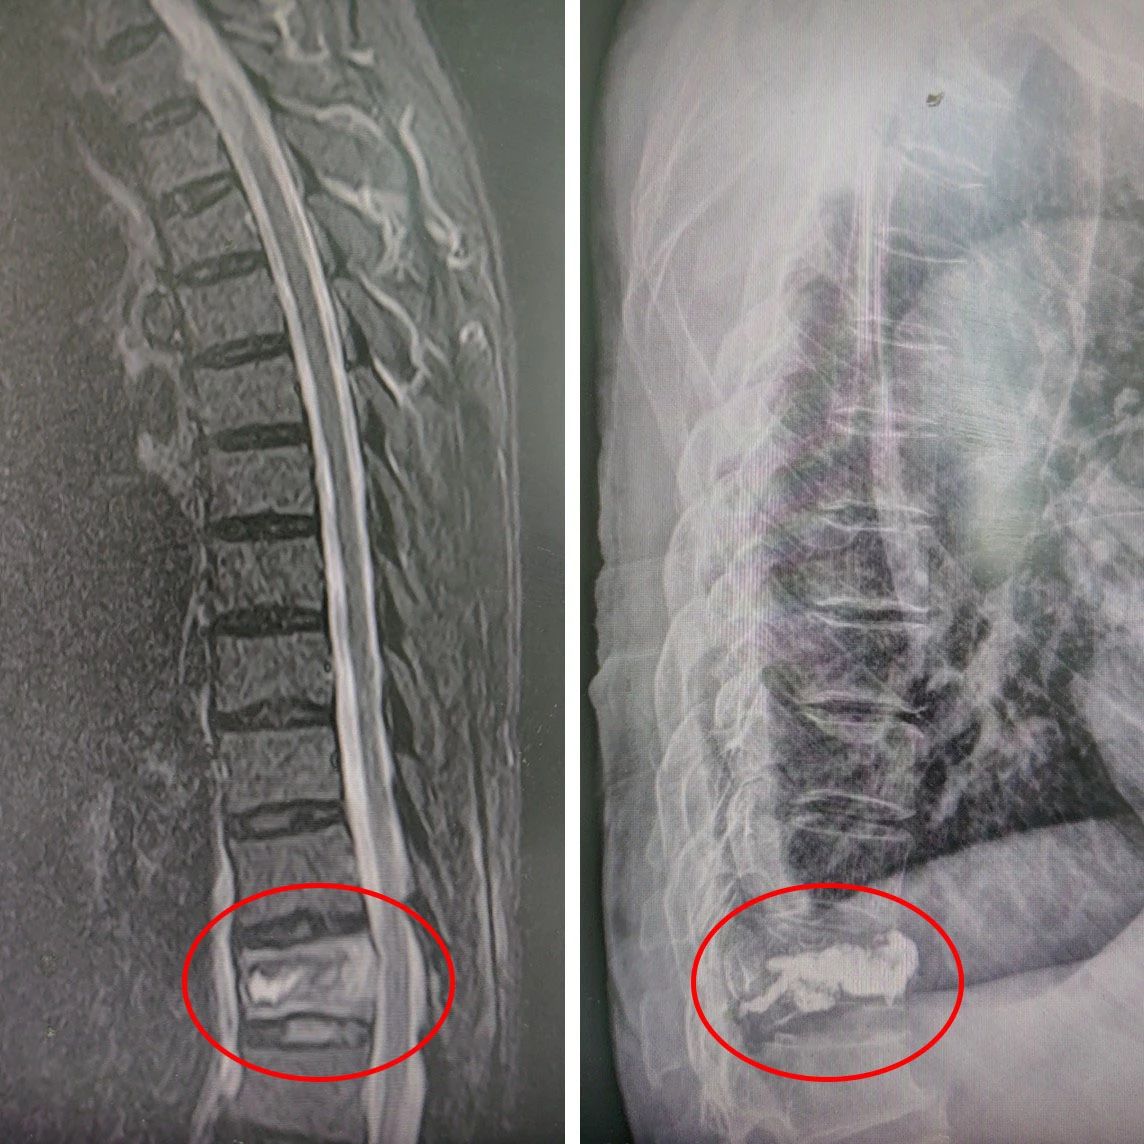

△ 术前:磁共振明确骨折 △ 术后:“骨水泥”已“就位”

数日前,吴先生(化名)在家中不慎摔倒,腰部遭受严重疼痛。在当地医院接受核磁共振检查后,发现第12胸椎出现骨折。巧的是,吴先生的妻子此前也曾遭遇胸腰椎骨折,并在我院由骨伤科华国军主任主刀进行手术治疗,术后恢复情况令患者十分满意。考虑到这次吴先生再次面临类似的骨伤问题,家里人一合计,决定将他从南通如皋老家连夜送至我院接受治疗。吴先生于17日晚上11点多抵达医院,并顺利办理了住院手续。经过对吴先生的身体状况进行全面评估,华国军主任决定采用经皮穿刺椎体后凸成形术(PKP)为其进行治疗。

手术于19日成功进行,术后吴先生的疼痛明显减轻,3天即顺利出院。对治疗效果极为满意的家属,特地制作了一面锦旗赠予骨伤科医护团队,以表达他们的感激之情。